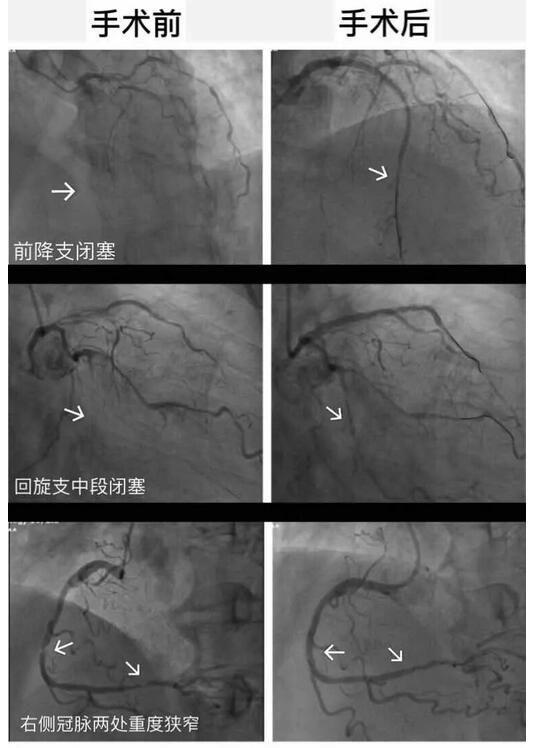

一次的手术并不能将贡大爷的病情完全缓解,按照术前心血管内科主任李东旺的设想。2017年的7月份,贡大爷的第二次手术顺利完成,血管全部贯通,并完全恢复健康。术后恢复健康的贡大爷,望着窗外的景色脸上露出了往日的笑容。

△手术前后对比图